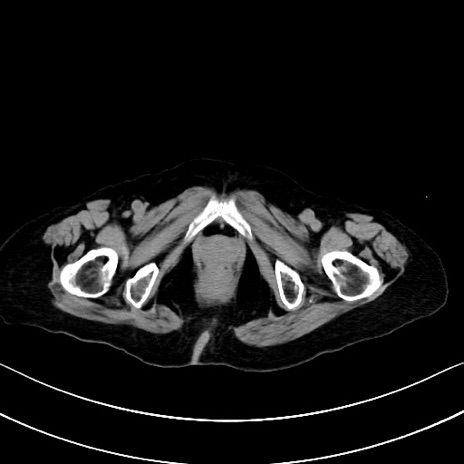

横断像

他院CT